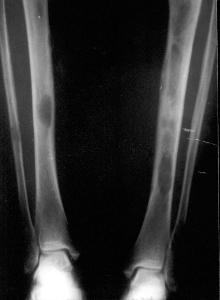

骨炎目前多认为是一种慢性病毒性感染。人体骨骼分为206块,不同部位骨头的炎症成因皆不同。其中致密性骨炎是一种骨质硬化性疾病,好发于20~25岁青年,女性多见,易累及髂骨、腰椎和骶骨邻近关节边缘部,单侧或双侧同时(先后)发病。